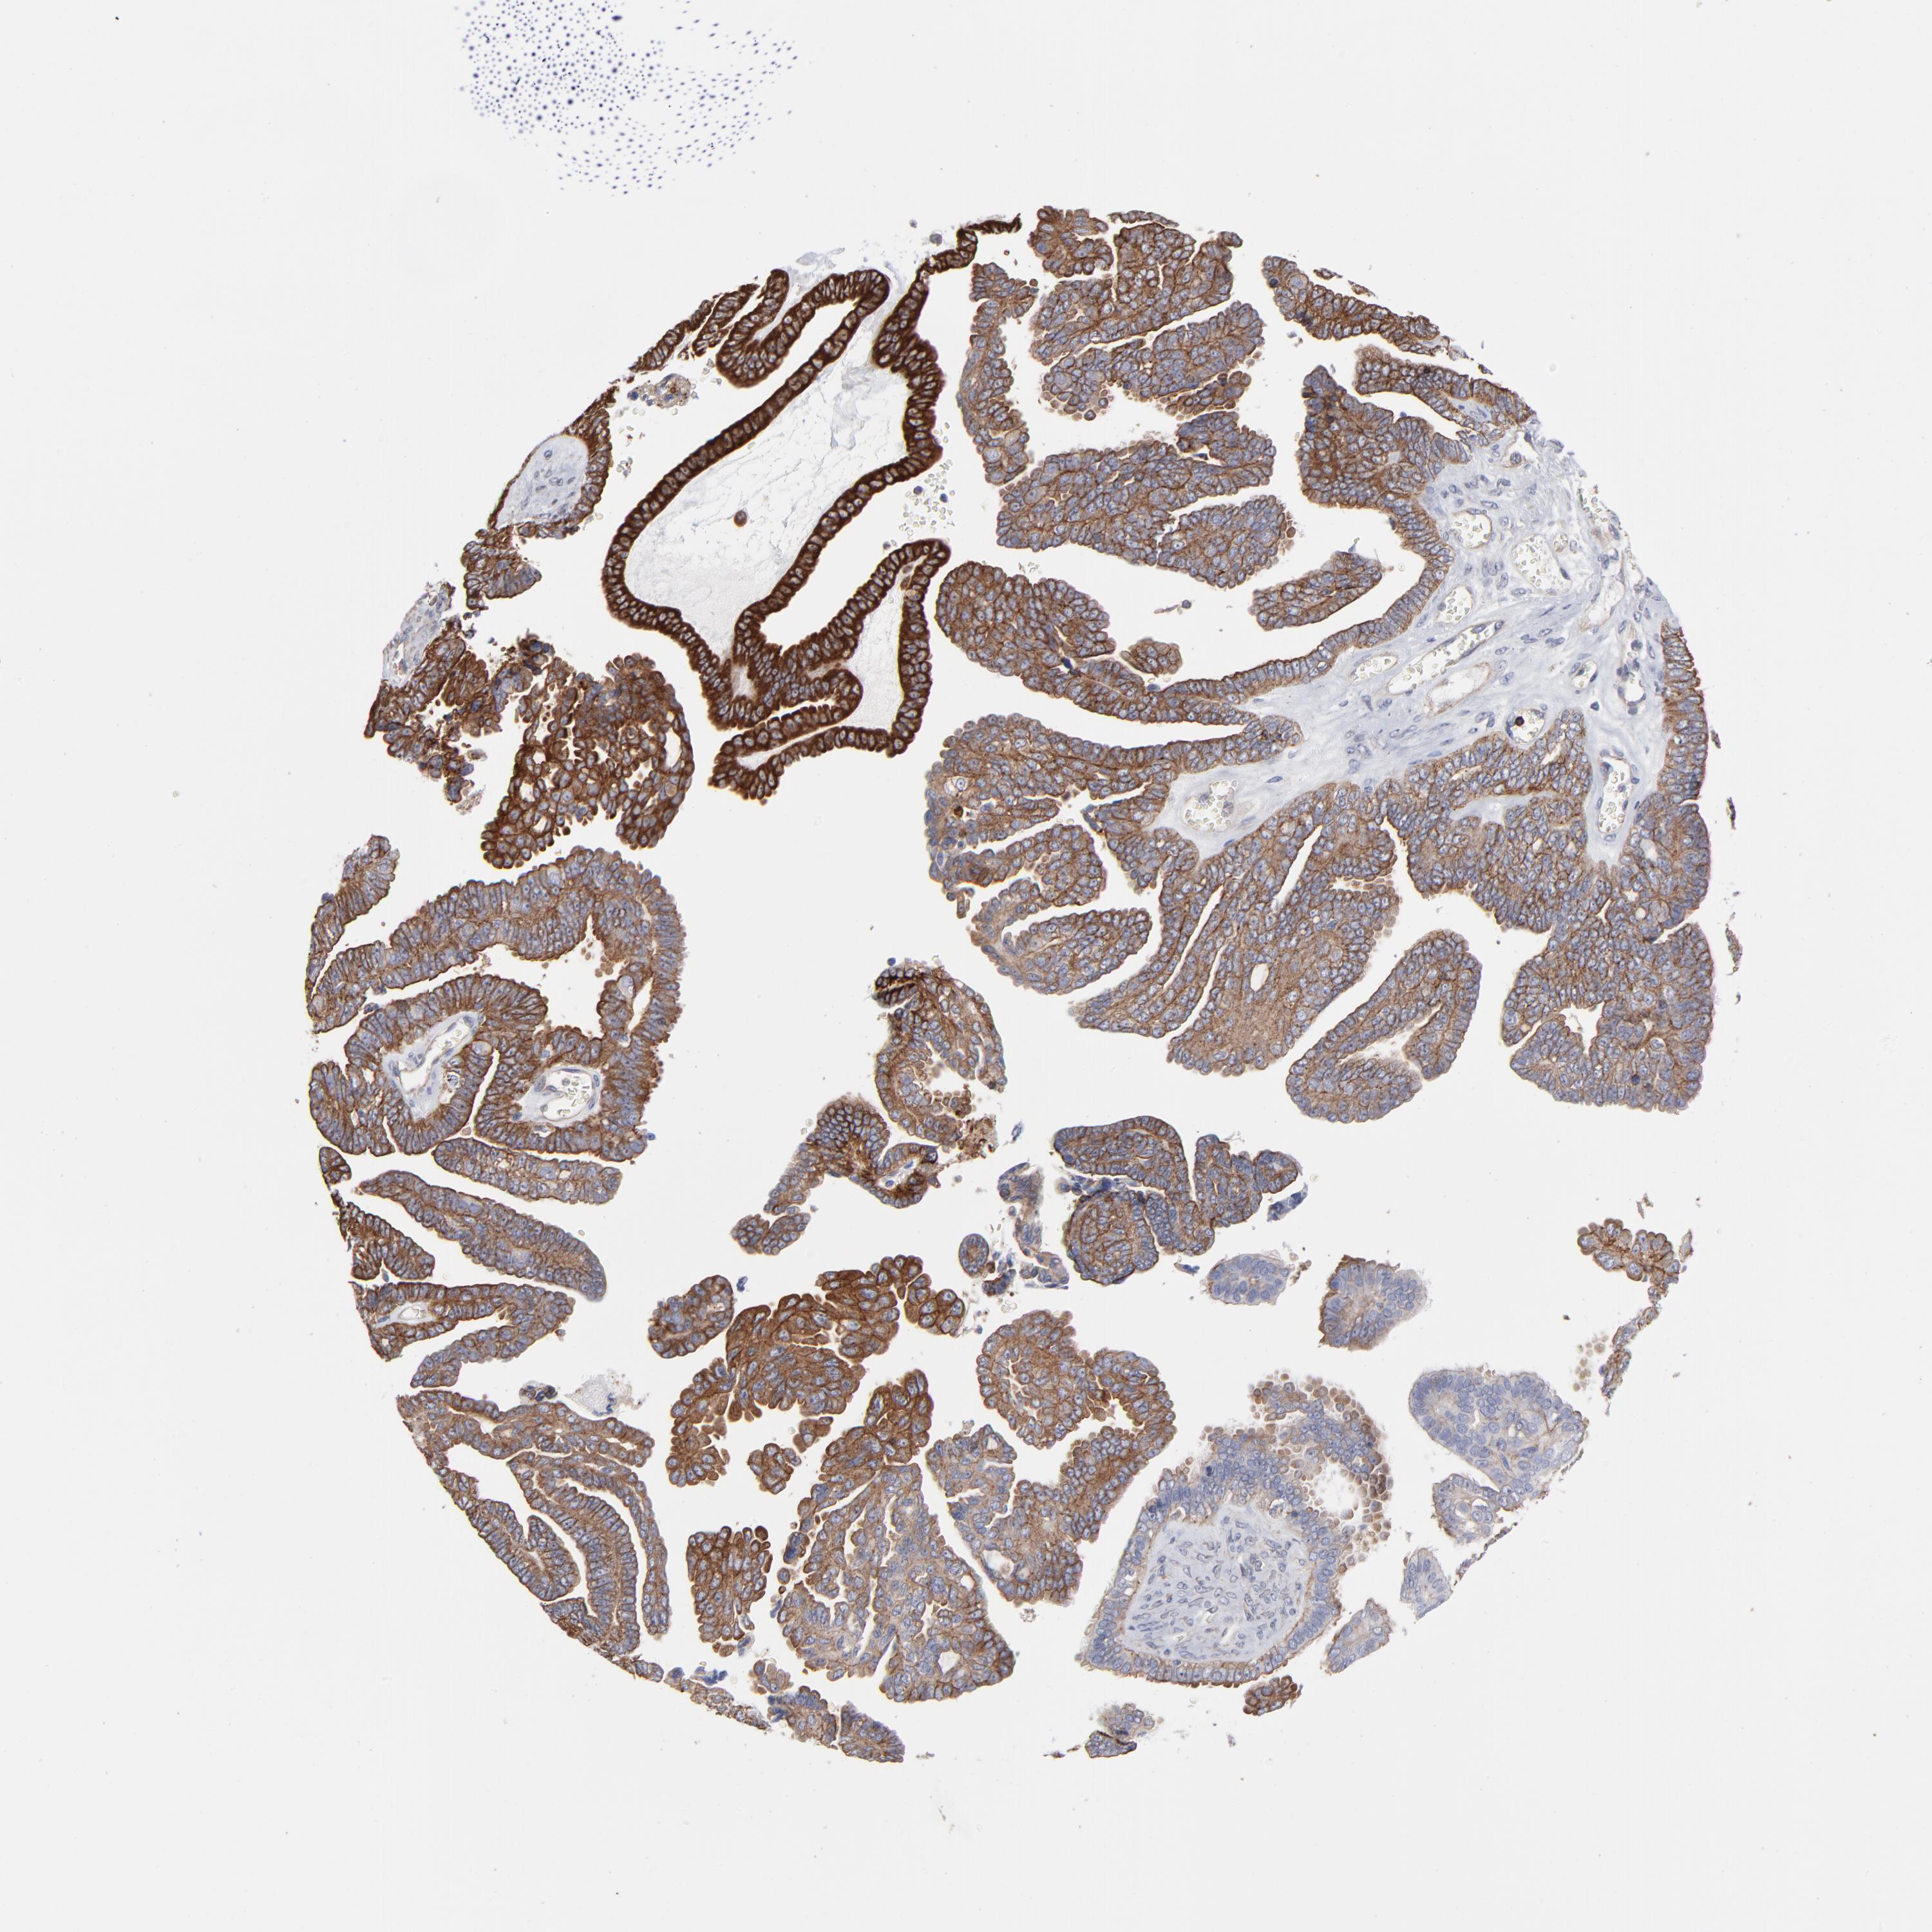

OVARIAN CANCER - Protein expressioni

A mouse-over function shows sample information and annotation data. Click on an image to view it in a full screen mode. Samples can be filtered based on level of antibody staining by selecting one or several of the following categories: high, medium, low and not detected. The assay and annotation is described here.

Note that samples used for immunohistochemistry by the Human Protein Atlas do not correspond to samples in the TCGA dataset.

Antibody stainingi

Antibody staining in the annotated cell types in the current human tissue is reported as not detected, low, medium, or high, based on conventional immunohistochemistry profiling in selected tissues. This score is based on the combination of the staining intensity and fraction of stained cells.

Each image is clickable and will lead to virtual microscopy that enables deeper exploration of all samples and also displays staining intensity scores, fraction scores and subcellular localization as well as patient and tissue information for each sample.

Antibody CAB003841

Staining

High

Medium

Low

Not detected

Intensity

Strong

Moderate

Weak

Negative

Quantity

>75%

75%-25%

<25%

None

Location

Nuclear

Cytoplasmic/membranous

Cytoplasmic/membranous,nuclear

Cystadenocarcinoma, mucinous, NOS

Carcinoma, endometroid

Cystadenocarcinoma, serous, NOS